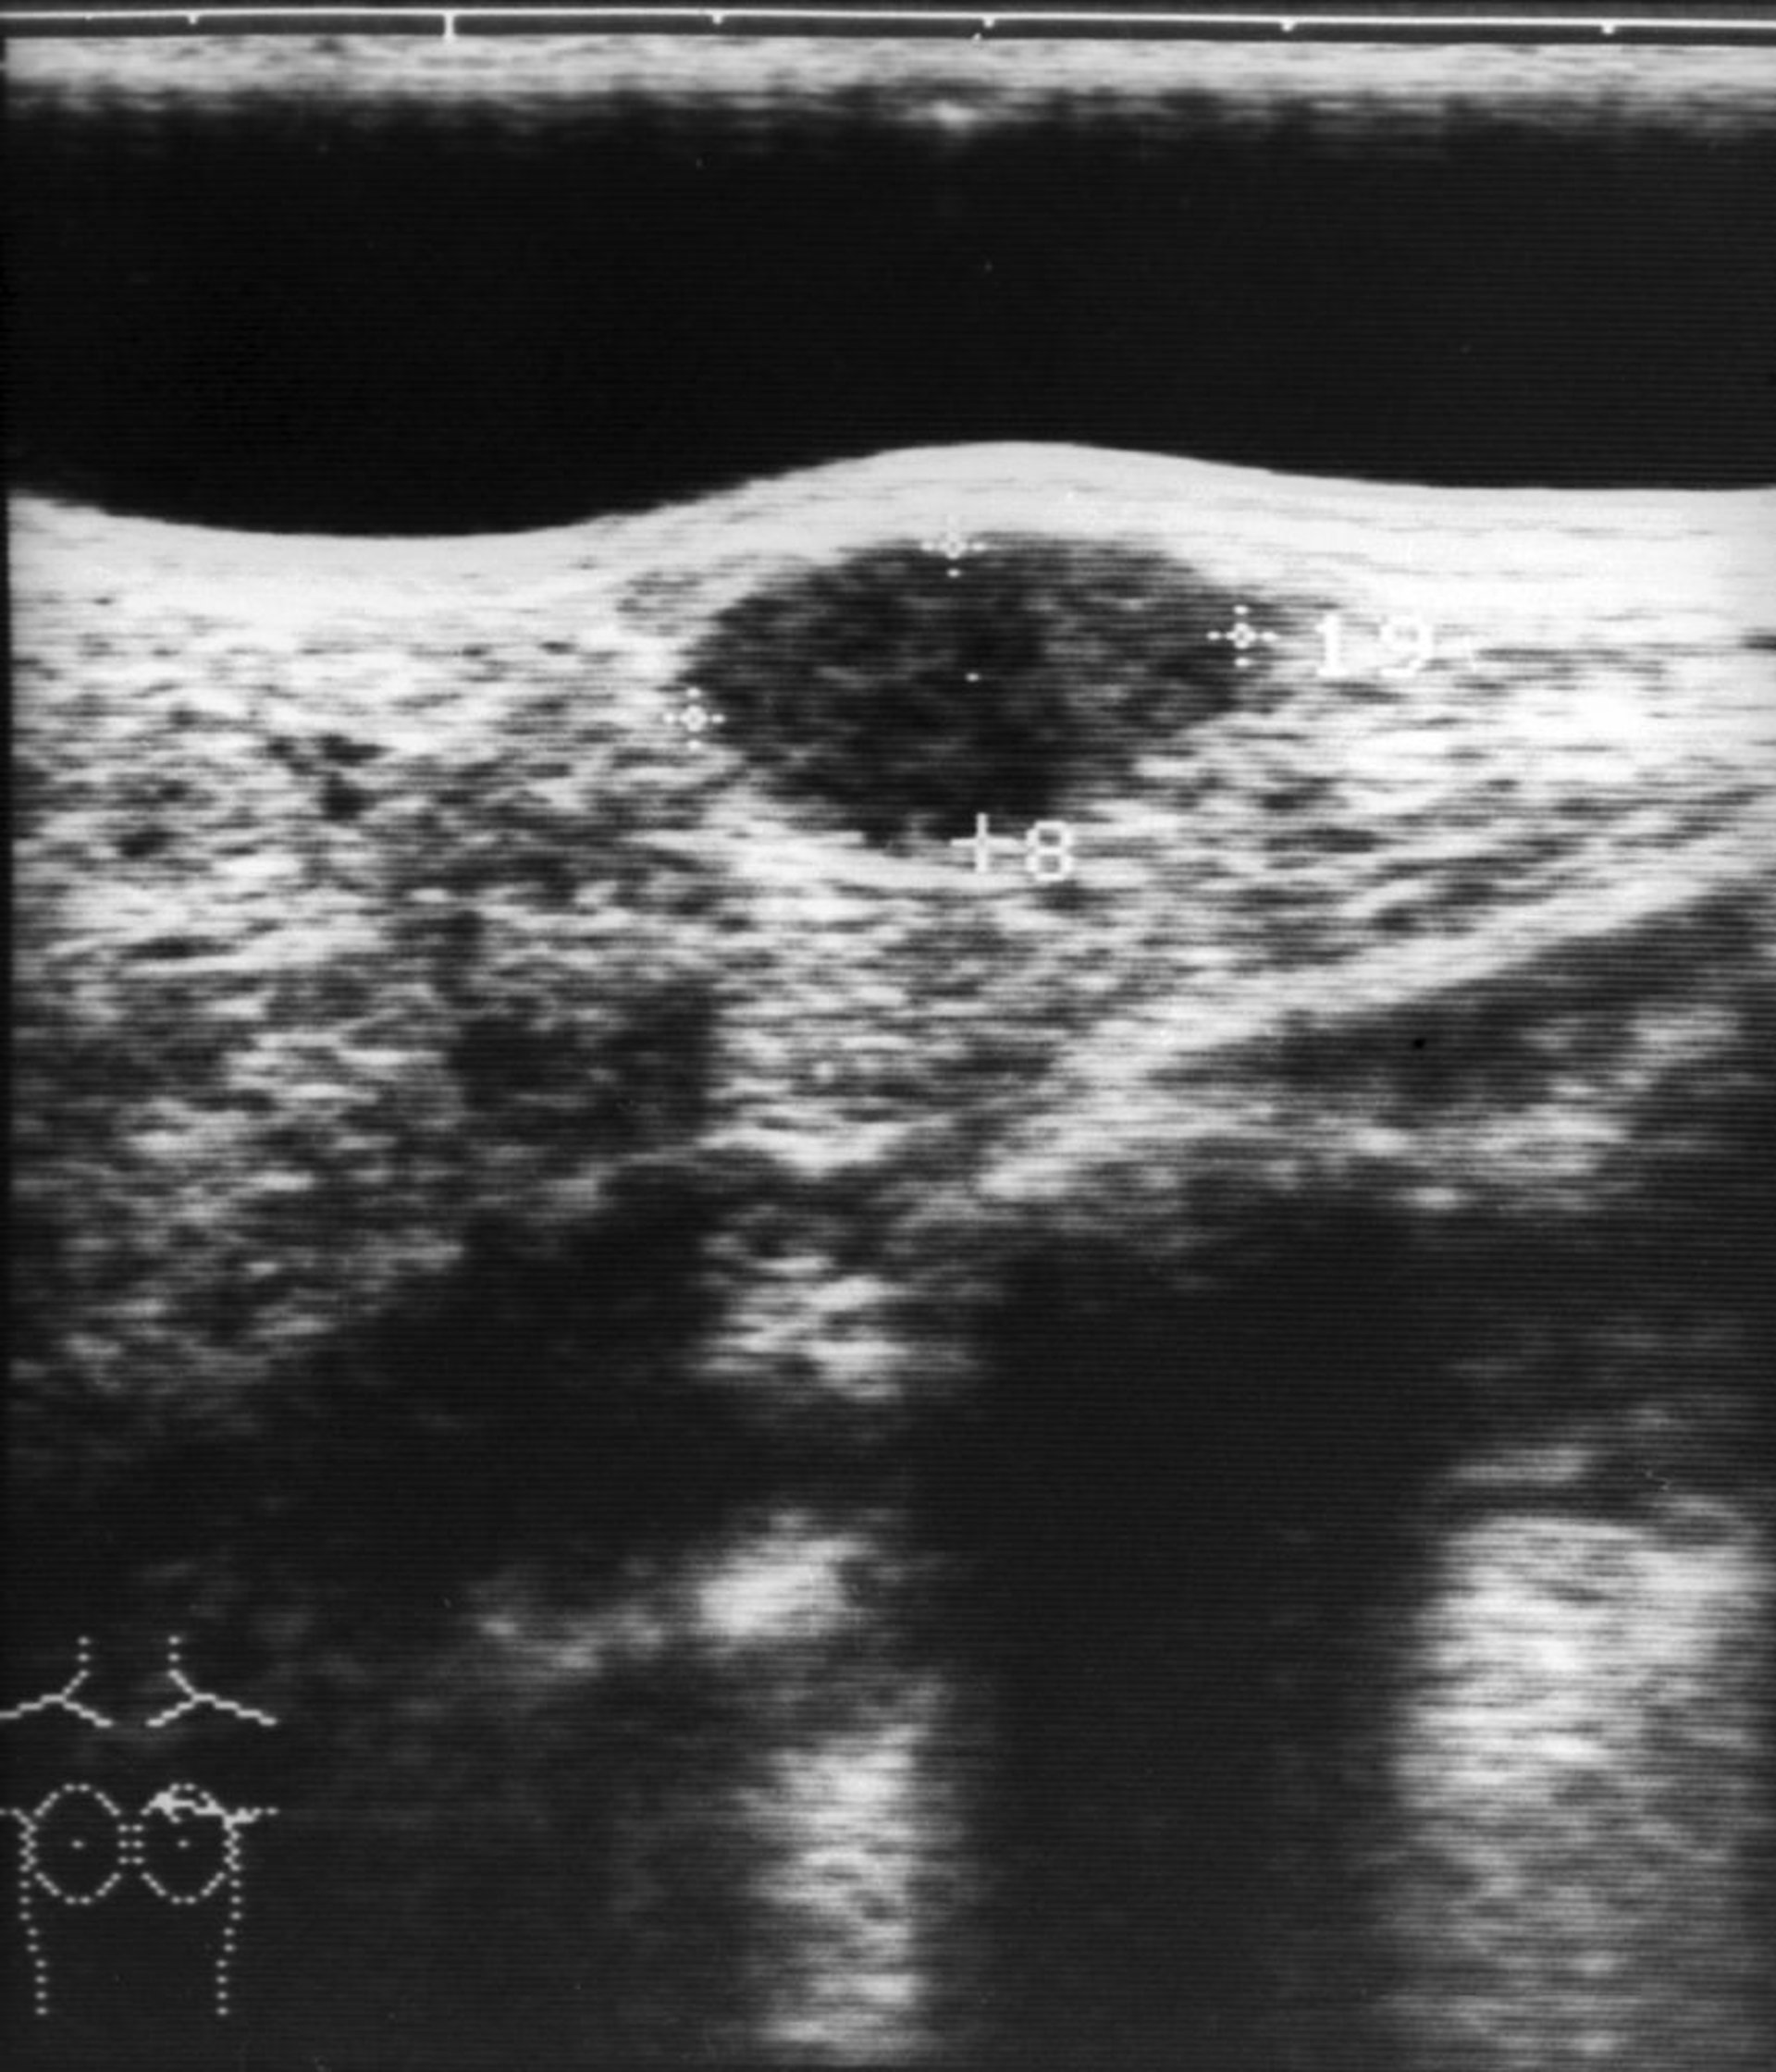

Dieses Bild zeigt eine Ultraschalluntersuchung eines Brustfibroadenoms (ovale hypoechogene Struktur in der oberen Bildmitte).